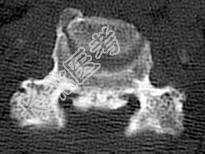

- 单项选择题女,58岁, 颈部疼痛,活动受限, 结合图像,最可能的诊断是 ( )

A、颈椎退行性变

B、颈椎结核

C、椎缘骨

D、椎间盘突出

E、局限性骨化性肌炎